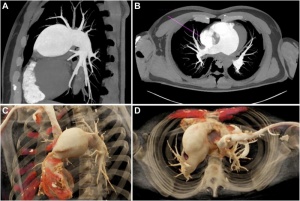

Изображенията, инфографиките и табличното представяне са важна част от медицинската енциклопедия на Фрамар, като имат за цел да помогнат на потребителите да разберат по-добре съдържанието. В някои статии се включват и мултимедийни елементи като видеоклипове и интерактивни инструменти с цел по-добро онагледяване.